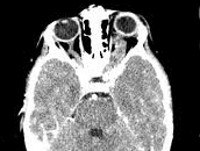

Наиболее достоверно глиома зрительного нерва диагностируется при помощи КТ головного мозга, которое позволяет визуализировать утолщенный зрительный нерв, определить границы разрастания опухоли и ее прорастание в полость черепа. При невозможности проведения КТ, используют прицельную рентгенографию черепа и рентгенографию орбиты, которые при интраорбитальной локализации глиомы выявляют одностороннее расширение полости орбиты и канала зрительного нерва, их затемнение, истончение стенок глазницы.